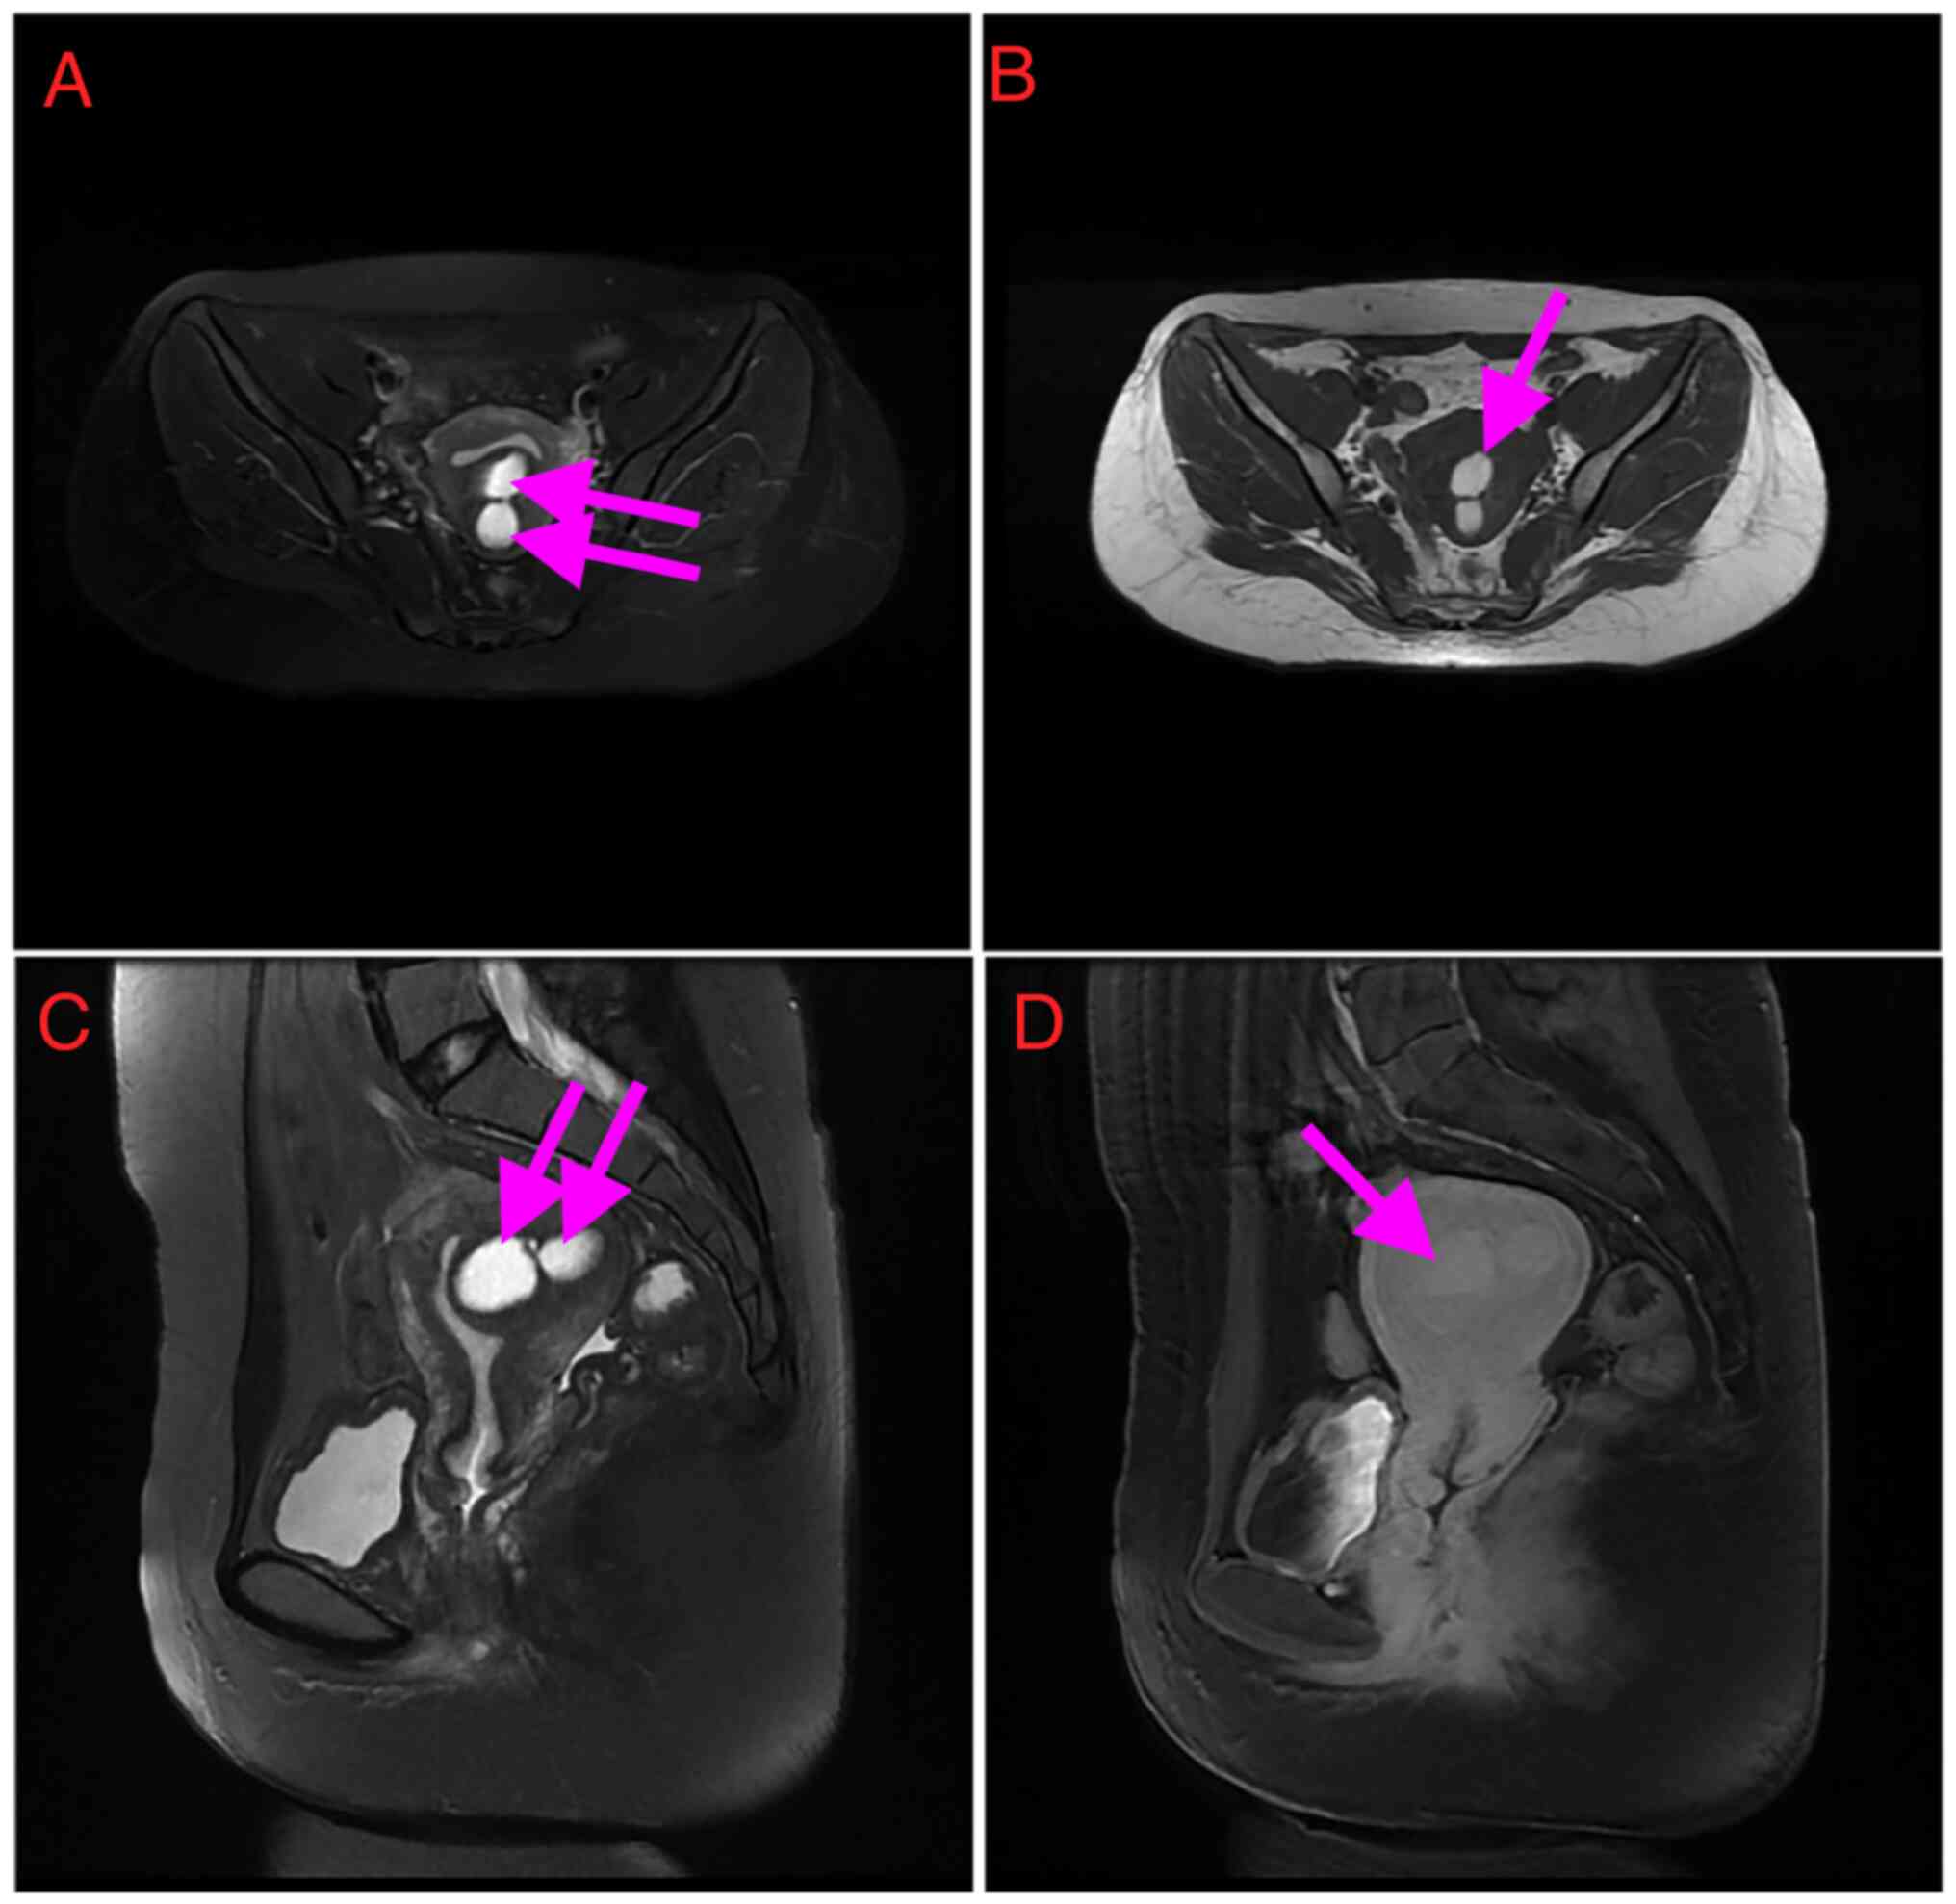

MRI findings. From the MRI findings (Fig. 2), the abnormal signal shadow and central hemorrhagic cystic in the posterior compartment of the uterus were considered adenomyoma. The mass measured 53x48x41 mm and T2-WI displayed the cyst as an area of high intensity. The normal uterine cavity was visualized as a line near the cyst. It was slightly hyperintense on T1- and T2-WI, with an internal fluid level, typical for the layering of simple and hemorrhagic or proteinaceous fluids.

Figure 2

Magnetic resonance imaging revealed the uterine adenomyotic cyst. (A) Axial T2-weighted image with fat suppression shows hyperintense lesion of uterine adenomyotic cyst (arrows). (B) Axial T1-weighted imaging. demonstrates the cystic lesion (arrows). (C) Sagittal T2-weighted image shows the hyperintense cystic lesion (arrows). (D) Sagittal contrast-enhanced T1-weighted image shows the cystic mass (arrows).